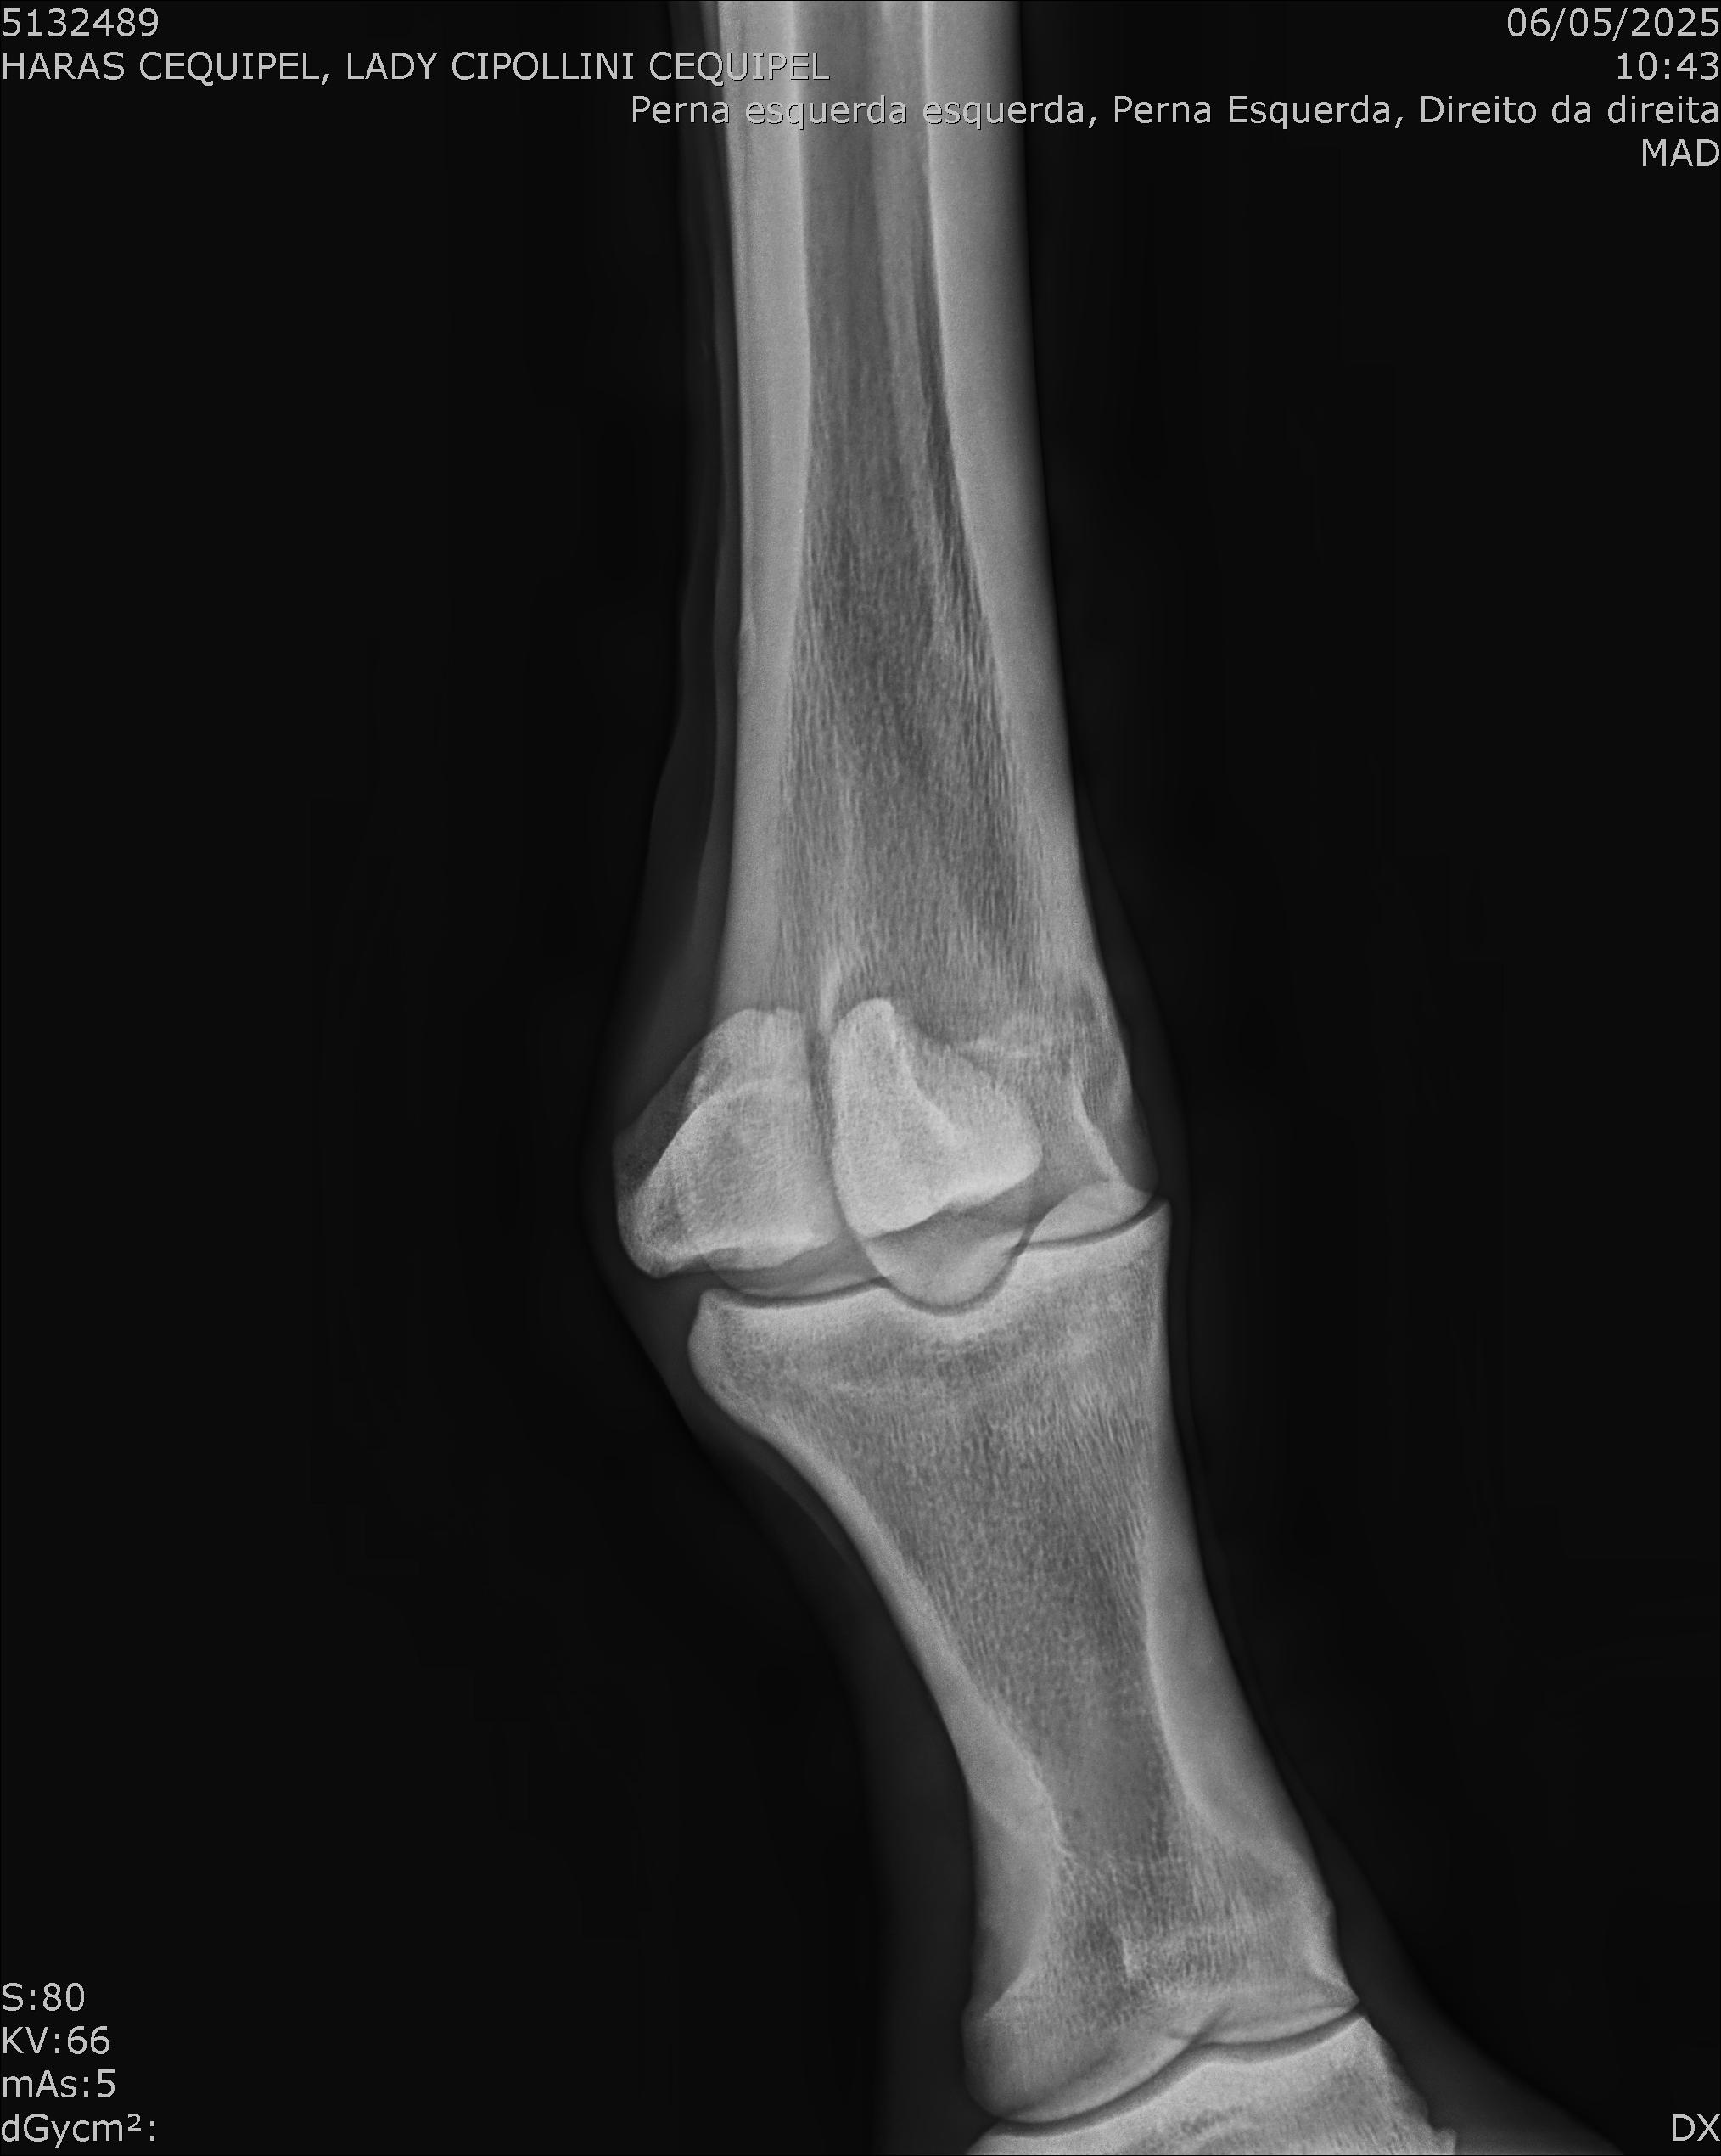

:: RAIOS-X DO LOTE